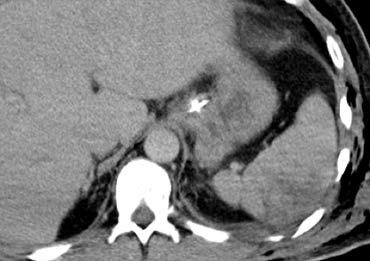

Trước tiên hãy quan sát các hình ảnh bên trái của bệnh nhân bị chấn thương gan.

Các dấu hiệu CT trong trường hợp này là gì?

Các dấu hiệu bao gồm:

- Tụ máu dưới bao gan lớn hơn 10 cm (tức là tổn thương độ 4)

- Vùng ngấm thuốc cản quang (contrast blush) (mũi tên)

- Không có tràn máu ổ bụng kèm theo

Vì vậy, mặc dù có thoát thuốc cản quang, bệnh nhân này sẽ được điều trị bảo tồn (không phẫu thuật) và có thể có tiên lượng tốt, do không có chảy máu vào khoang phúc mạc.

Thoát thuốc cản quang có ý nghĩa đặc biệt quan trọng, nhất là khi kết hợp với tràn máu ổ bụng.